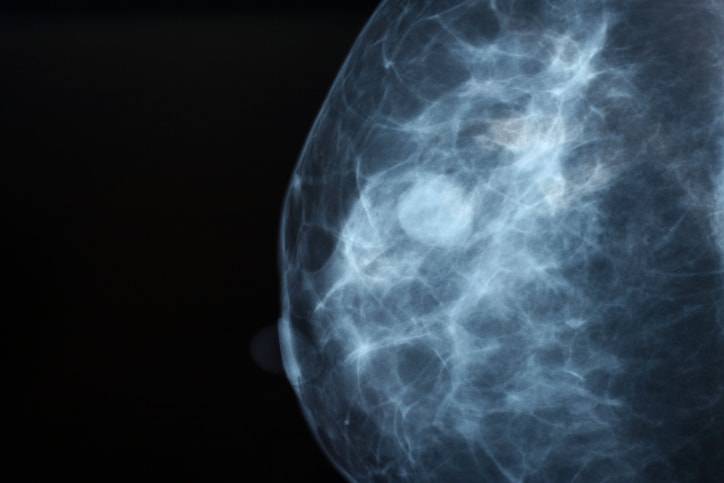

Il tumore al seno non è solo uno, ne esistono di diversi tipi e con differente gravità. Tra questi, il più grave e difficile da curare, è il cancro al seno triplo negativo, una forma molto aggressiva e mortale che rappresenta il 10-20% dei tumori al seno e colpisce soprattutto le donne più giovani.

Non esiste una sola tipologia di cancro al seno, ne esistono diverse. Tra queste quella più grave e mortale è il carcinoma mammario triplo negativo, un tumore molto aggressivo che negli ultimi tempi ha ucciso diverse giovani donne, anche famose, come la giornalista della BBC Rachel Bland, di cui hanno parlato i media in questi giorni.

Il cancro al seno triplo negativo (TNBC, dall’inglese triple-negative breast cancer) è così chiamato perché le sue cellule tumorali sono negative sia ai recettori ormonali di estrogeni (ER) e progesterone (PR) sia ai recettori della proteina HER2, fattore di crescita epiteliale. Questi recettori, presenti negli altri tipi di cancro al seno, sono i bersagli delle cure contro il tumore. Spesso, infatti, queste molecole sono presenti in eccesso sulla superficie delle cellule tumorali e sono responsabili dell’incontrollata proliferazione cellulare, in seguito a stimolazione ormonale e del fattore di crescita epiteliale. Per curare dunque i tumori positivi ai recettori ormonali si interviene con la terapia ormonale, per ridurre la crescita delle cellule tumorali, insieme alle altre cure contro il cancro. Se le cellule tumorali, invece, sono positive alla proteina HER2 si interviene con trattamenti di ultima generazione, come anticorpi monoclonali e inibitori tirosin-chinasi anti-HER2 (farmaco biologico trastuzumab).

Nel caso del cancro al seno triplo negativo (mancano i recettori ormonali di estrogeni e progesterone e quelli della proteina HER”), non ci sono bersagli specifici da colpire con terapie mirate. Il tumore viene curato con la chemioterapia, che tuttavia non dà risultati soddisfacenti. Inoltre, questo tipo di tumore tende a essere maggiormente aggressivo e a formare metastasi più facilmente. Ecco spiegato il motivo per cui questo tipo di cancro è molto difficile da curare e ha una elevata mortalità.